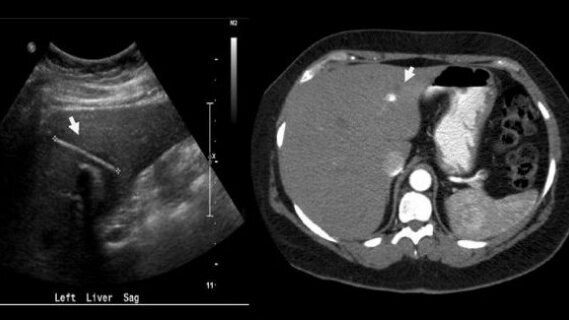

Volgens de artsen van de afdeling Chirurgie van Dalhousie University werd de vrouw opgenomen op de spoedeisende hulp met een lichaamstemperatuur van bijna 39°C, misselijkheid, overgeven en hypertensie. Een abdominale echo toonde een leverabces en de aanwezigheid van een hard object.

Een paar uur later werd de patiënt overgebracht naar de intensive care vanwege ademhalingsproblemen en een systeeminfectie door bloedvergiftiging. De vrouw kreeg gedurende meerdere weken een uitgebreide antibioticabehandeling. Een CT-scan wees uit dat het om een tandenstoker ging van 4,1 cm lang en een paar millimeter breed, waarna een laparoscopische chlolecystectomie werd uitgevoerd. De patiënt herstelde snel en zes maanden na de operatie voelde ze zich nog steeds goed.